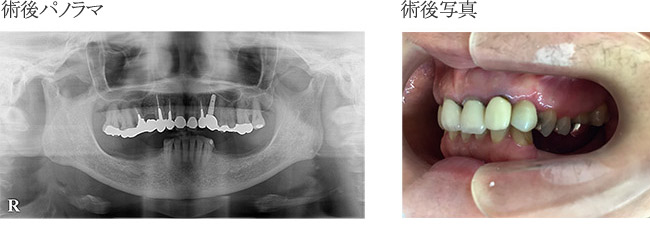

гӮӨгғігғ—гғ©гғігғҲз—ҮдҫӢ

з—ҮдҫӢпј‘

еӨ–еӮ·гҒ«гӮҲгӮҠжӯҜеҶ дҝ®еҫ©еҫҢгҖҖзҹҜжӯЈз”ЁгғҜгӮӨгғӨгғјгҒ«гҒҰеӣәе®ҡ

гҒқгҒ®еҫҢгҖҖжӯҜж №з ҙжҠҳгӮ’иө·гҒ“гҒ—з–јз—ӣгӮ’зҷәз”ҹгҒ—гҒҹгҒҹгӮҒгӮ„гӮҖгҒӘгҒҸжҠңжӯҜгҖӮ

гҒ•гӮүгҒ«гҒқгҒ®еҫҢгҖҖгӮӨгғігғ—гғ©гғігғҲгҒ«гӮҲгӮҠдҝ®еҫ©гҒ—гҒҹз—ҮдҫӢ

иЎ“еҫҢ

| в‘ жІ»зҷӮеҗҚ | дәӨйҖҡдәӢж•…гҒ«гӮҲгӮӢеүҚжӯҜз ҙжҠҳгҖӮгӮӨгғігғ—гғ©гғігғҲгҒ«гӮҲгӮӢдҝ®еҫ© |

|---|---|

| в‘ЎиІ»з”Ё | гӮёгғ«гӮігғӢгӮўгҒ«гӮҲгӮӢеүҚжӯҜдҝ®еҫ©пјҲгӮөгғјгӮёгӮ«гғ«гӮ¬гӮӨгғүдҪҝз”Ёз—ҮдҫӢпјүпј“пјҗдёҮеҶҶпјҸжң¬ |

| в‘ўжңҹй–“ | пј“жңҲпј‘пјҳж—ҘжҠңжӯҜгҖҒпј–жңҲпј‘пјҷж—ҘгӮӘгғҡгҖҒпјҷжңҲпј’пјҳж—ҘTEKгӮ»гғғгғҲгҖҒпј‘пјҗжңҲпј‘пј‘ж—ҘгӮёгғ«гӮігғӢгӮўгӮ»гғғгғҲгҖҖе®ҢдәҶгҒҫгҒ§зҙ„пј—гҒӢжңҲ |

| в‘ЈйҖҡйҷўй »еәҰ | гӮӘгғҡеҫҢгҒҜзҝҢж—Ҙжҙ—жө„гҖҒпј‘йҖұй–“еҫҢиҰіеҜҹгҖҒгҒ•гӮүгҒ«пј‘йҖұй–“еҫҢжҡ«й–“зҫ©жӯҜгҒ®зўәиӘҚгҖҒиӘҝж•ҙгҖҒпј‘гҒӢжңҲеҫҢзўәиӘҚгҖҒжё…жҺғгҖҒгҒӮгҒЁпј‘гҒӢжңҲгҒ”гҒЁгҒ«зўәиӘҚгҖҒпјҷжңҲгҒ«PTVгҒ«гҒҰгӮӘгӮ№гғҶгӮӘгӮӨгғігғҶгӮ°гғ¬гғјгӮ·гғ§гғігҒ®зўәиӘҚгҖҒеҚ°иұЎгҖҒTEKиЈ…зқҖгҖҒзҙ„пј’йҖұй–“еҫҢгҖҖгӮёгғ«гӮігғӢгӮўгӮ»гғғгғҲ |

| в‘ӨжӮЈиҖ… | пј’пјҗд»ЈгҖҖеҘіжҖ§ |

| в‘ҘжІ»зҷӮеҶ…е®№ | иҮӘи»ўи»ҠгҒЁи»ҠгҒ®дәӨйҖҡдәӢж•…гҒ§еүҚжӯҜгӮ’жү“ж’ІгҖҒи…«и„№гҖӮжҡ«й–“еӣәе®ҡгҒ§еӣәе®ҡгҒ§гҒҚгӮӢгҒҢжӯҜж №з ҙжҠҳгҒ®гҒҹгӮҒж №з®ЎжІ»зҷӮгӮ’гҒҠгҒ“гҒӘгҒЈгҒҹгҒҢз ҙжҠҳз·ҡгҒҢеәғгҒҢгӮҠжҠңжӯҜгӮ’дҪҷе„ҖгҒӘгҒҸгҒ•гӮҢгҒҹгҖӮиӢҘгҒ„еҘіжҖ§гҒ§гҒӢгҒӨеүҚжӯҜпј’жң¬гҒ®гҒҹгӮҒгӮёгғ«гӮігғӢгӮўдҝ®еҫ©гӮ’гҒҷгӮӢгҒ“гҒЁгҒ«гҒӘгҒЈгҒҹгҖӮ |

| в‘ҰжІ»зҷӮзөҗжһң | еҜ©зҫҺзҡ„гҒ«гӮӮж©ҹиғҪзҡ„гҒ«гӮӮжӮЈиҖ…гҒ•гӮ“гҒ”жң¬дәәгҒҢжәҖи¶ігҒ§гҒҚгӮӢзөҗжһңгҒЁгҒӘгҒЈгҒҰгҒҠгӮҠе®ҡжңҹжӨңиЁәгӮ’гҒҠйЎҳгҒ„гҒ—гҒҰгҒ„гӮӢгҖӮ |

| ⑧注ж„ҸзӮ№ | еүҚжӯҜгҒ®гҒҹгӮҒеҜ©зҫҺзҡ„гҒ«гӮӮж©ҹиғҪзҡ„гҒ«гӮӮеӣ°гӮүгҒӘгҒ„гӮҲгҒҶгҒ«гӮөгғјгӮёгӮ«гғ«гӮ¬гӮӨгғүгӮ’дҪҝз”ЁгҒ—гҒҹгҖӮгҒ“гӮҢгҒ«гӮҲгӮҠиЎ“еүҚгҒ«жӮЈиҖ…гҒ•гӮ“гҒ«дәҲжё¬гӮ’иҰӢгҒҰгҒ„гҒҹгҒ гҒҸгҒ“гҒЁгҒҢгҒ§гҒҚе®үеҝғгҒ«гӮӮгҒӨгҒӘгҒҢгҒЈгҒҹгҒЁиҖғгҒҲгҒҰгҒ„гӮӢгҖӮгҒ„гҒҫгҒ®гҒЁгҒ“гӮҚеӨ§дёҲеӨ«гҒ§гҒҷгҒҢгӮ№гӮ№гӮҜгғӘгғҘгғјеӣәе®ҡгҒ®зӮәдёҮгҒҢдёҖиў«гҒӣгҒ®гӮёгғ«гӮігғӢгӮўгҒ«гғҲгғ©гғ–гғ«гҒҢзҷәз”ҹгҒ—гҒҰгӮӮдҝ®зҗҶгҒҷгӮӢгҒ«гҒҜжҜ”ијғзҡ„е®№жҳ“гҒЁжҖқгӮҸгӮҢгӮӢгҖӮ |